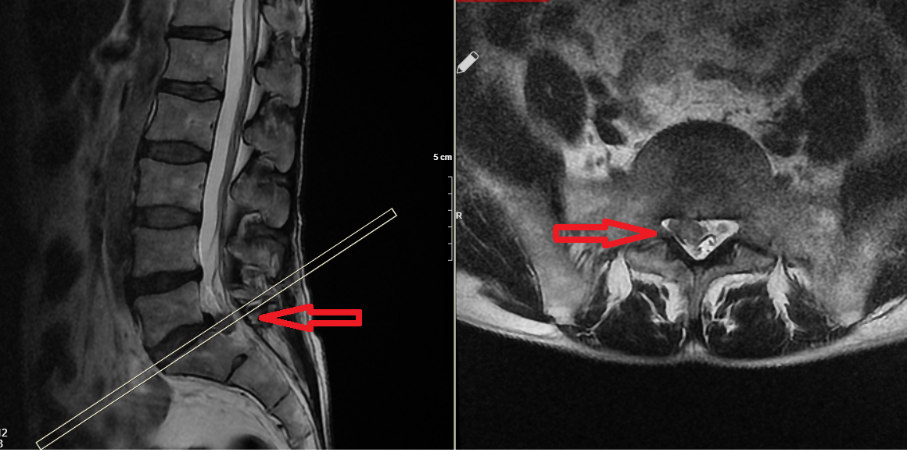

- MRG (Manyetik Rezonans Görüntüleme): Disk yapısındaki hasarı ve sinir sıkışmasını en net şekilde gösterir.

Tanıda, hastanın klinik belirtileriyle görüntüleme sonuçlarının örtüşmesi önemlidir.